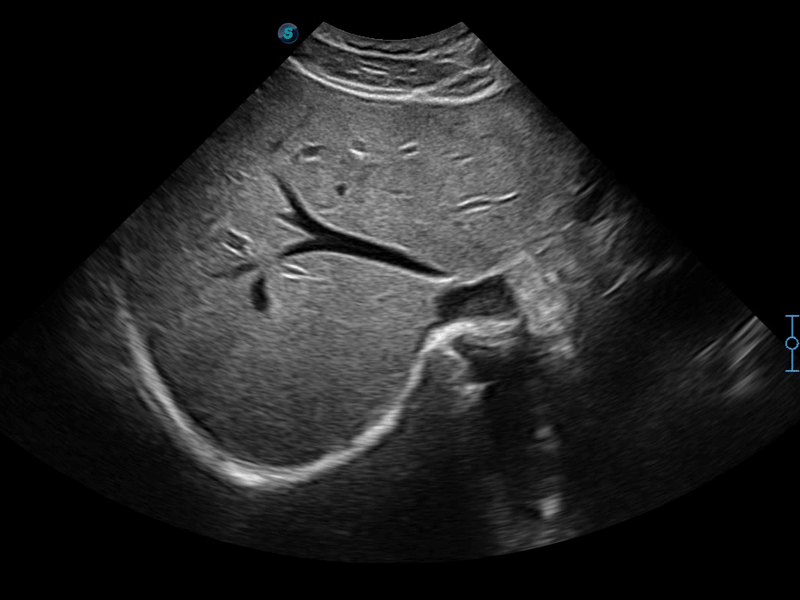

扩展成像技术

凸阵、线阵和相控阵探头进行实时扫描时,开启扩展成像模式,可以扩展超声图像视野,以便更完整地查看大的病灶或组织器官的解剖结构。

实时宽景成像技术

通过彩色血流和实时宽景相结合,可观察到完整的动静脉血流,方便医生检查。实时扫查过程中,如有任何操作失误也可以很容易地进行回扫擦除,而不会中断扫查。